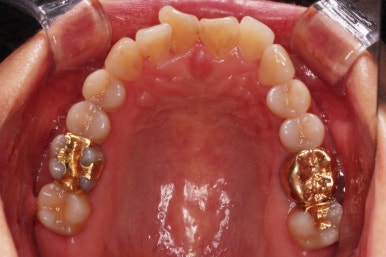

동래임플란트교정 초진 시 입안의 모습입니다.

치열이 전반적으로 삐뚤어져 있는 양상이고요.

아랫니가 윗니보다 더 많이 삐뚤어 있는데요.

임플란트가 이미 있을 경우

임플란트는 교정이 되지 않습니다.

뼈에 단단히 붙어 있기 때문에 힘을 줘도 원하는 위치로 이동되지 않습니다.

이번 환자분의 경우 임플란트가 어금니 크기보다 작게 제작이 되어 있어서 추후에 교합을 맞추기도 곤란한 상황이었어요.

그래서 교정 후에 임플란트 뿌리 부분은 그대로 사용하고 머리 부분만 재제작 하기로 했습니다.